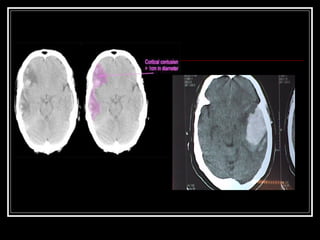

Contusão cerebral

 São lesões traumáticas focais e superficiais causadas pelo

atrito entre o cérebro e o crânio no momento do trauma;

 São muito comuns na face orbitária dos lobos frontais e

região anterior dos lobos temporais;

 Geralmente apresenta lesão parenquimatosa com graus

variáveis de hemorragia, edema e necrose;

 Ocorrem déficits neurológicos que persistem por mais de

24h;

 Não costumam deixar seqüelas importantes, mas podem

originar focos epileptogênicos e resultar em anosmia por

lesão dos bulbos e nervos olfativos;

 Padrão ouro para diagnostico é a ressonância magnética.

Contusão cerebral  Sãolesões traumáticas focais e superficiais causadas pelo atrito entre o cérebro e o crânio no momento do trauma;  São muito comuns na face orbitária dos lobos frontais e região anterior dos lobos temporais;  Geralmente apresenta lesão parenquimatosa com graus variáveis de hemorragia, edema e necrose;  Ocorrem déficits neurológicos que persistem por mais de 24h;  Não costumam deixar seqüelas importantes, mas podem originar focos epileptogênicos e resultar em anosmia por lesão dos bulbos e nervos olfativos;  Padrão ouro para diagnostico é a ressonância magnética.